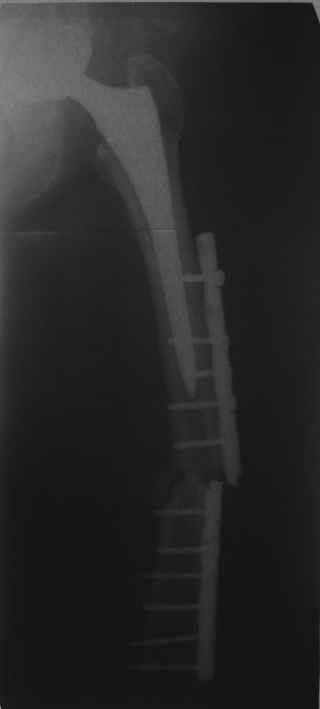

Обещанные ранее снимки Заранее спасибо.

Это сплошной титановый стержень. На дистальном конце отверстия под кондуктор. На другом - канал под ножку глубиной 60 мм, стенки толщиной 2,5-3 мм. И там же продольный пропил, чтобы канал мог адаптироваться к ножке.

Сейчас опорную нагрузку на бедро берет на себя система от бедренного компонента эндопротеза до проксимального винта в интрамедуллярном гвозде. Свидетельство тому - реакция кортикала утолщением вокруг того самого винта. Таким образом вся кость от верхушки б.вертела до проксимального винта не испытывает физиологической осевой нагрузки. Результатом этого могут стать следующие последствия друг друга не исключающие: 1) все будет хорошо до перелома опорной системы по винту(ам) или в месте соединения штифта с ножкой или еще где-либо, 2) исключенная из-под нагрузки кость будет терять в количестве и качестве, что не очень (или очень не) хорошо для возможных будущих ревизий (тьфу-тьфу!!!).

Хотел бы обратить Ваше внимание, что реакция кортикала наблюдается только вокруг проксимального винта, дистальный винт не испытывает подобной нагрузки. Отсюда еще одна умозрительная авантюра - выкрутить только проксимальный винт. Изменения кости вокруг дистального винта тоже могут дать ответ на счет интеграции ножки, также как и появляется возможность сломать его. Страховаться (затратнее, но надежнее) или нет(легче, но не безопасно) динамическим винтом - на Ваш выбор.

О качестве сращения перелома тоже сказать трудно. Выраженной мозоли нет. В боковой проекции отломки накладываются друг на друга. В прямой проекции зона перелома в наружной части закрылась не полностью. Возможно причина тому - недогрузка кости.